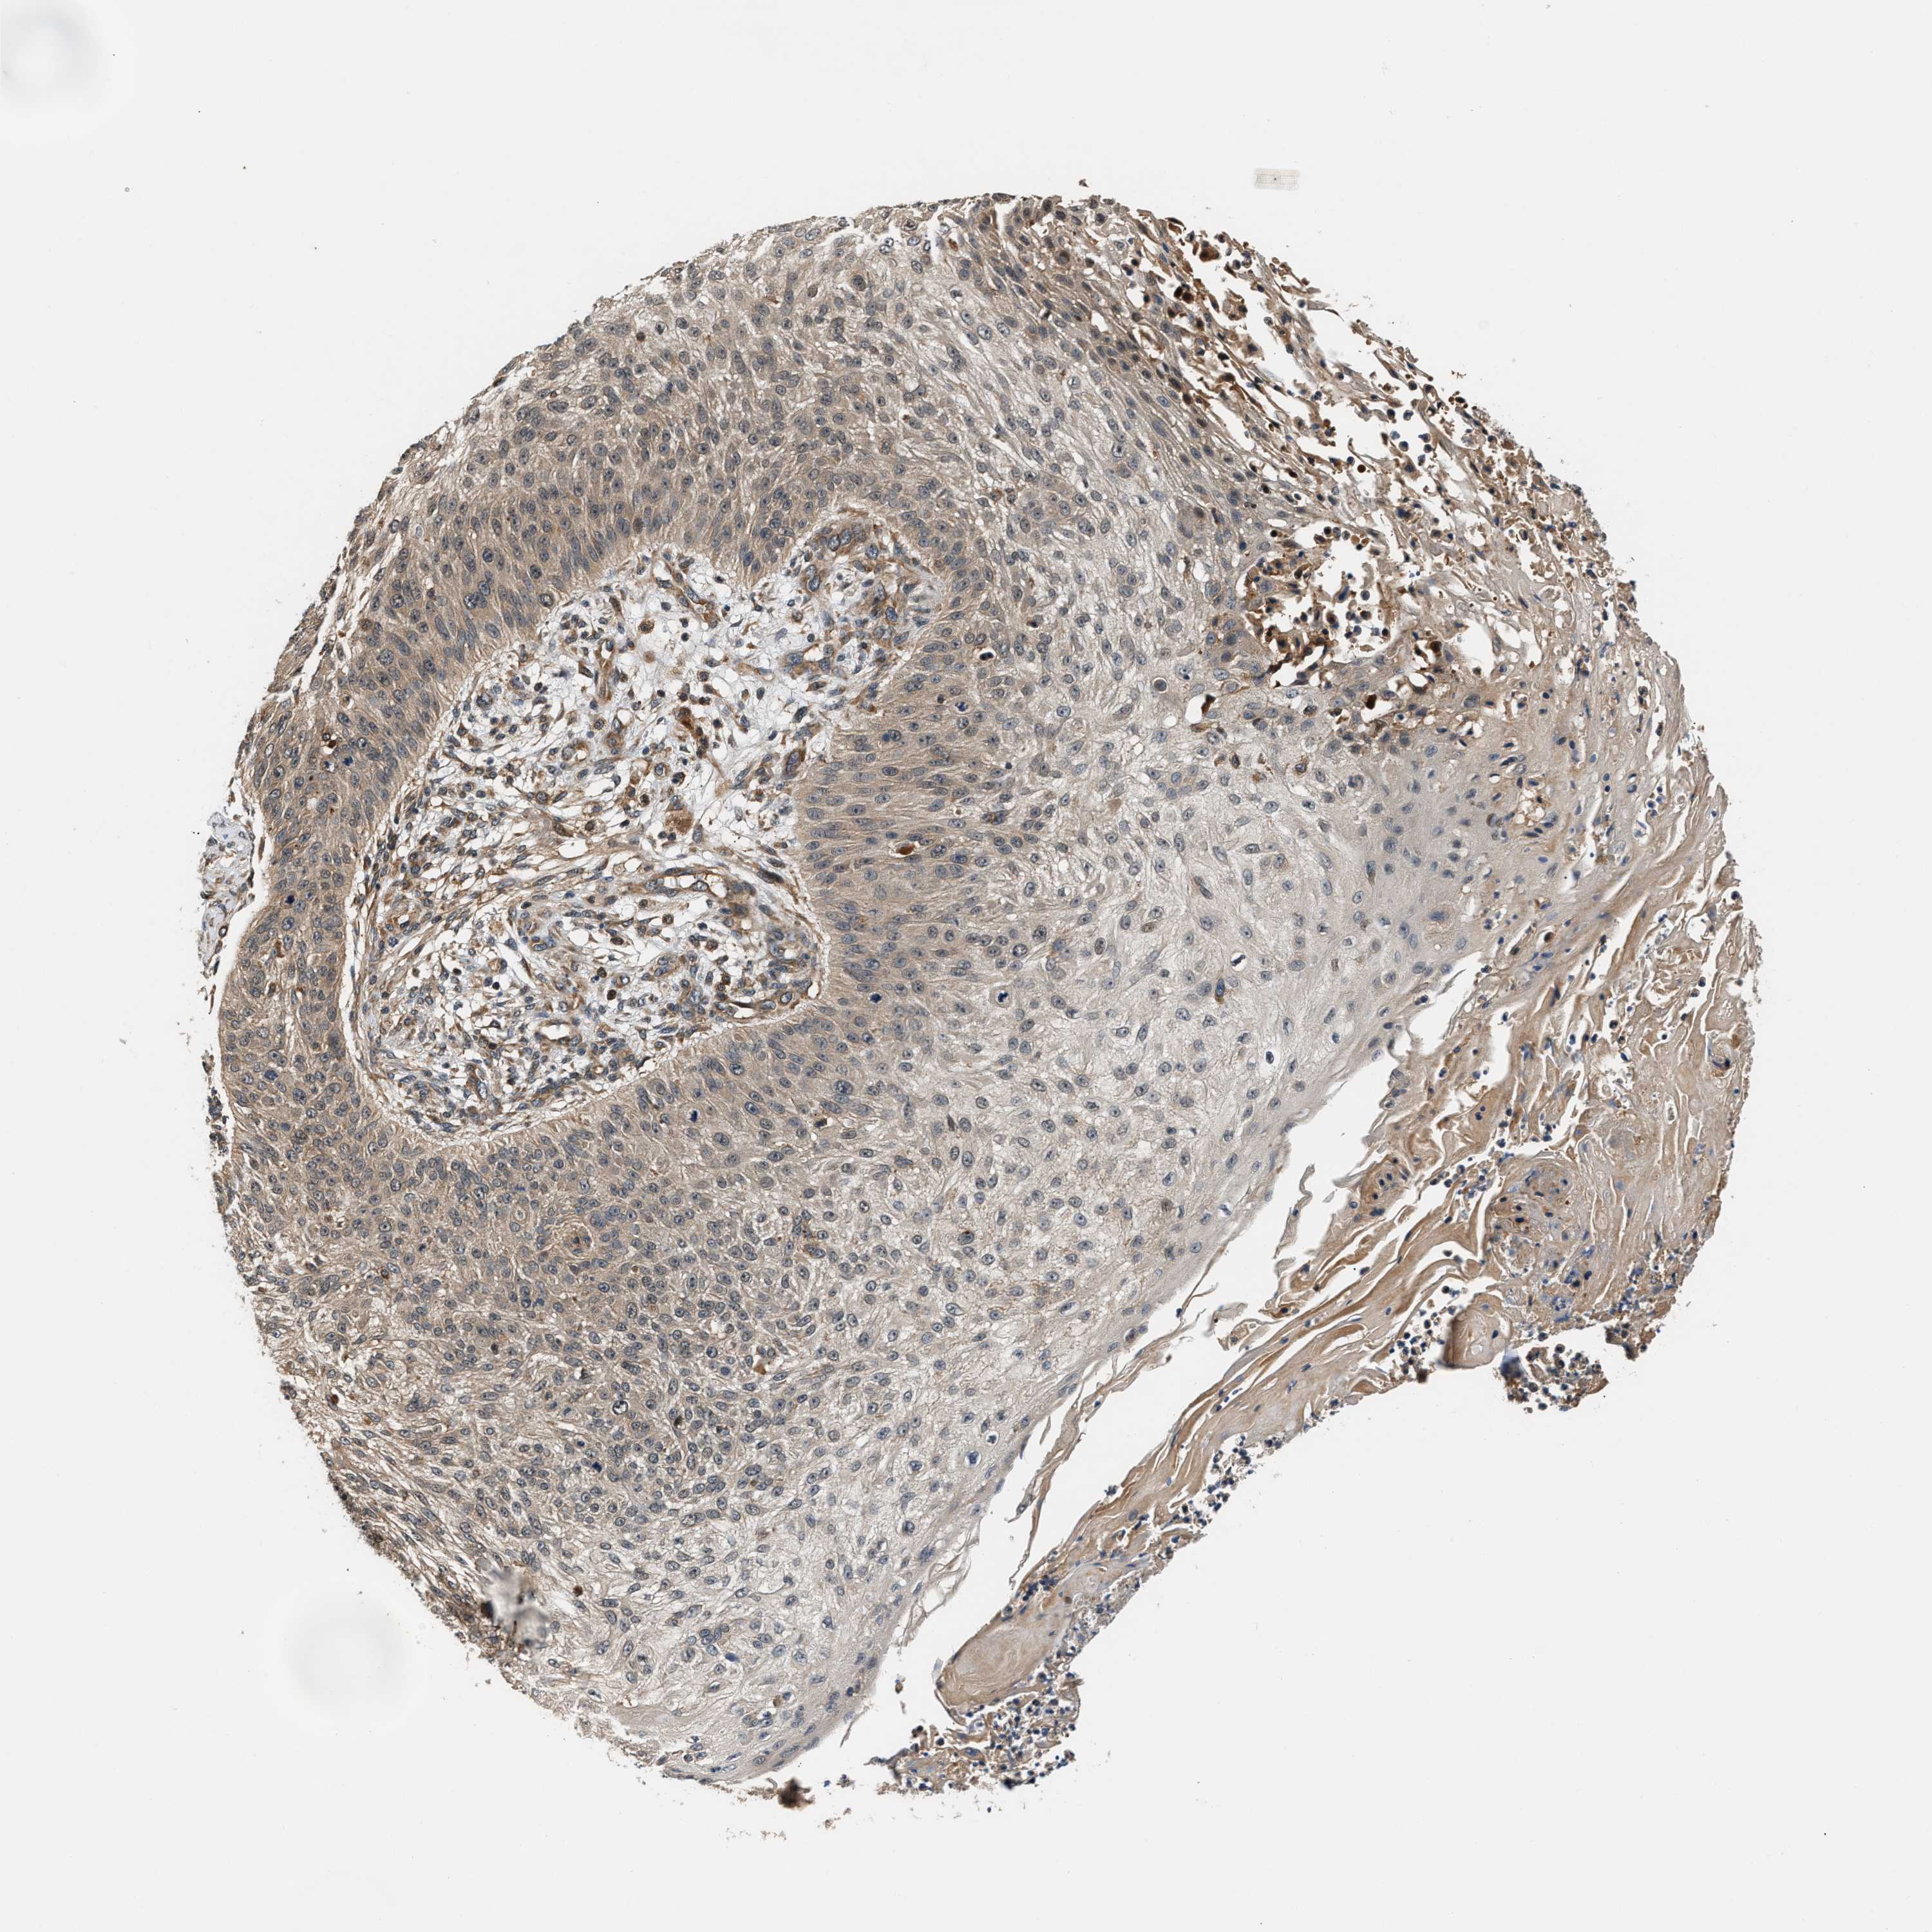

SKIN CANCER - Protein expressioni

A mouse-over function shows sample information and annotation data. Click on an image to view it in a full screen mode. Samples can be filtered based on level of antibody staining by selecting one or several of the following categories: high, medium, low and not detected. The assay and annotation is described here.

Antibody stainingi

Antibody staining in the annotated cell types in the current human tissue is reported as not detected, low, medium, or high, based on conventional immunohistochemistry profiling in selected tissues. This score is based on the combination of the staining intensity and fraction of stained cells.

Each image is clickable and will lead to virtual microscopy that enables deeper exploration of all samples and also displays staining intensity scores, fraction scores and subcellular localization as well as patient and tissue information for each sample.

Antibody HPA020615

Staining

High

Medium

Low

Not detected

Intensity

Strong

Moderate

Weak

Negative

Quantity

>75%

75%-25%

<25%

None

Location

Nuclear

Cytoplasmic/membranous

Cytoplasmic/membranous,nuclear

Squamous cell carcinoma in situ, NOS